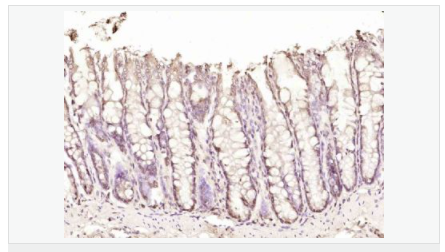

Rabbit anti-DAP1 Polyclonal antibody

交叉反應(yīng):Human,Rat(predicted:Mouse,Dog,Pig,Cow,Horse,Sheep) 推薦應(yīng)用:IHC-P,IHC-F,IF,ELISA

產(chǎn)品描述

英文名稱DAP1

中文名稱死亡相關(guān)蛋白1抗體

別    名DAP 1; DAP; DAP-1; DAP1_HUMAN; Death associated protein 1; Death associated protein; Death-associated protein 1.

研究領(lǐng)域細胞生物  信號轉(zhuǎn)導(dǎo)  細胞凋亡

抗體來源Rabbit

克隆類型Polyclonal

交叉反應(yīng)Human, Rat,  (predicted: Mouse, Dog, Pig, Cow, Horse, Sheep, )

產(chǎn)品應(yīng)用ELISA=1:5000-10000 IHC-P=1:100-500 IHC-F=1:100-500 IF=1:100-500 (石蠟切片需做抗原修復(fù))

分 子 量11kDa

細胞定位細胞核 細胞漿

免 疫 原KLH conjugated synthetic peptide derived from human DAP1:61-102/102

產(chǎn)品介紹his gene encodes a basic, proline-rich, 15-kD protein. The protein acts as a positive mediator of programmed cell death that is induced by interferon-gamma.

Negative regulator of autophagy. Involved in mediating interferon-gamma-induced cell death.

Phosphorylated. Phosphorylation by MTOR inhibits the suppressive activity of DAP toward autophagy.